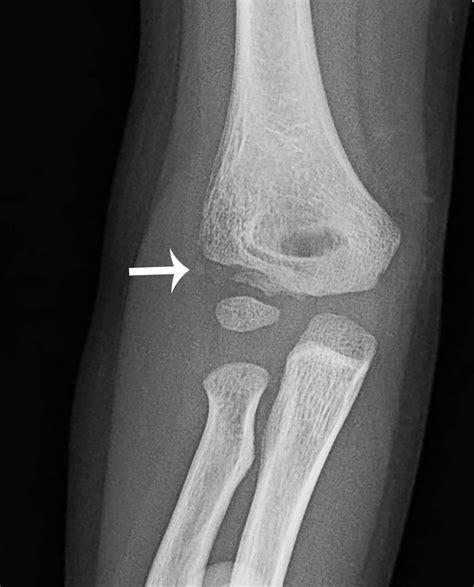

Diagnosing a Medial Epicondyle Fracture

Diagnosing a Medial Epicondyle Fracture involves a combination of physical examination and imaging tests. The diagnostic process typically includes:

• Physical Examination: The healthcare provider will assess the elbow for swelling, tenderness, and range of motion. They may also check for any deformities or instability in the joint.

• Imaging Tests: X-rays are the primary imaging tool used to diagnose a Medial Epicondyle Fracture. They can reveal the location and extent of the fracture. In some cases, additional imaging such as a CT scan or MRI may be required to provide a more detailed view of the injury.

Accurate diagnosis is crucial for determining the appropriate treatment plan.